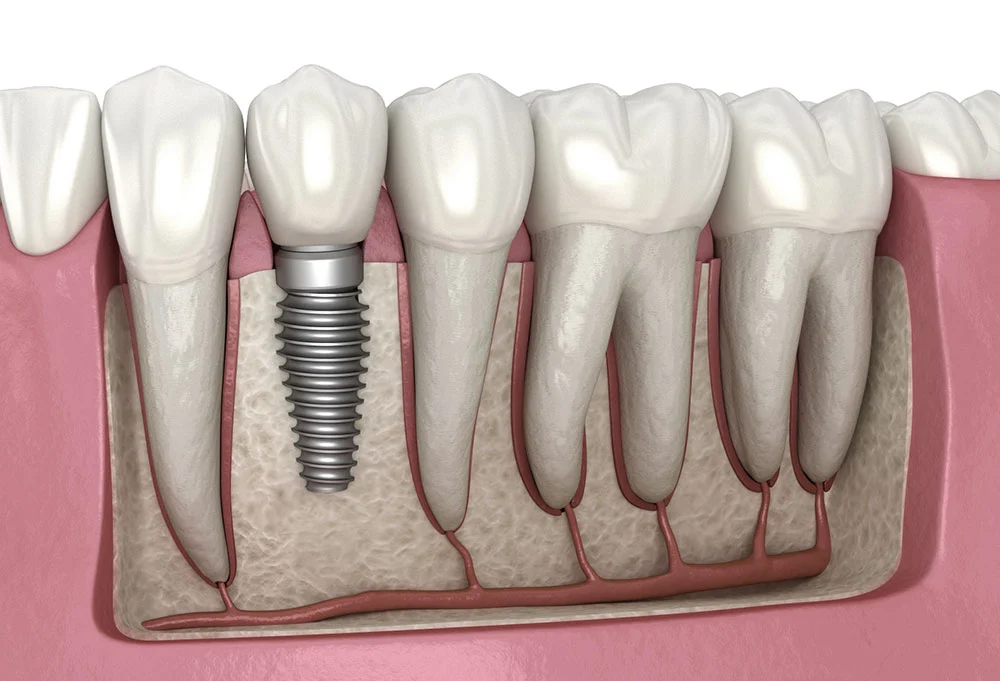

Dental implants are titanium roots placed in the jawbone to replace missing teeth. Once integrated with the bone, they support a crown, bridge, or full restoration that looks and functions like natural teeth.

They are considered the most reliable and durable solution for tooth replacement, preserving both bone and surrounding teeth.